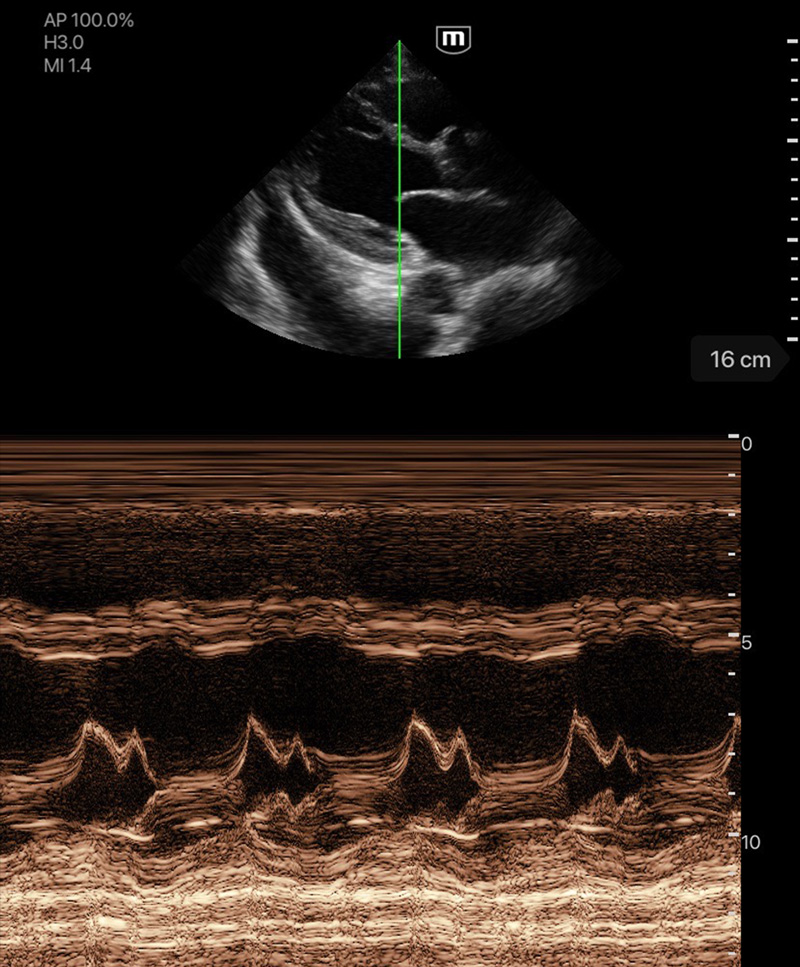

Професионално качество на диагностичните изображения

Различни режими на изображението

Множество режими за сканиране

M mode

Клинични снимки